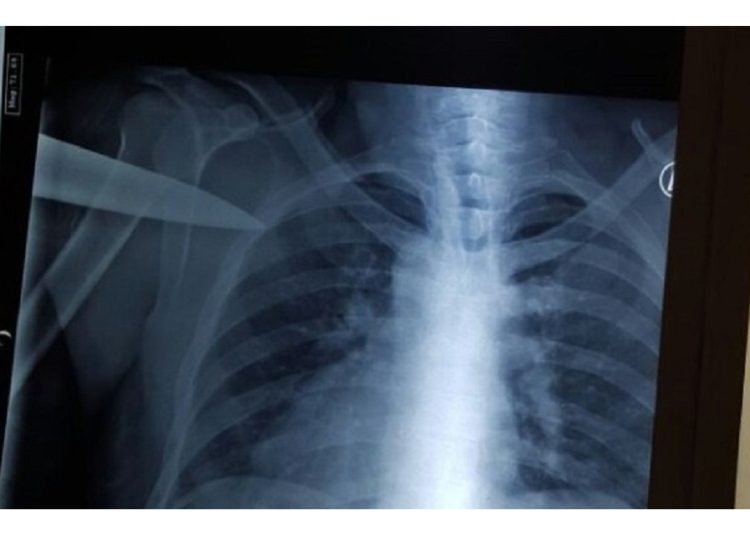

Sin atender las indicaciones del personal, Vladímir siguió caminando y poco antes de llegar a la salida afirmó que quería fumar, a pesar de estar semidesnudo, sin cigarillos y con el cuchillo aún en la espalda. Todos los llamamientos fueron infructuosos hasta que un médico le espetó: «¿Adónde va? ¡Va a morir!», momento en el que recapacitó y aceptó regresar.

Desde el servicio de prensa del Ministerio de Sanidad de la república de Tartaristán informaron que el hombre recibió finalmente la asistencia médica que necesitaba y se encuentra estable.